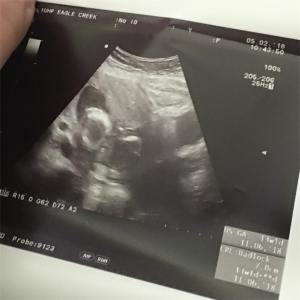

That day will forever be burned into my memory. At 14 weeks, my OB had not been able to find the heartbeat on the doppler and had taken me for an ultrasound. She found him right away on the screen, kicking, and waving directly at us. When I went in for my 18 week ultrasound, she couldn’t find a heartbeat on the doppler. I should have known then that that was unusual. Anxiety whispered in my ear that my baby was dead and to brace myself for the truth, but I brushed that away and walked confidently to the ultrasound room, feeling only a little worried.

She found him quickly. There he was on the screen. I could make out his head and his body, but he looked odd. He was all curled up, floating there, still. My OB took a deep breath and let it out in an audible rush of air. And I knew.

While my OB attempted to get some femur measurements to see how long ago he had passed, that was the moment that filled my mind. I had no reason to think that he had been gone at that point. I thought I had felt a real kick for the first time just days before the photo shoot. But somehow, I knew. And laying on that table, silently sobbing while she took measurements and the buzzing and whirring of the printer printing off the last photos of him I would ever have, what little innocence and blind joy that may have remained in thinking that any trimester was safe, left me indefinitely.

We didn’t know yet when we lost him that our baby was a boy. I just knew that he would be. We did chromosome testing and found out weeks later that he was a boy, and that there was nothing wrong with him or the placenta from what they could see. No chromosomal abnormalities. Normal placenta. No large clots or anything suspicious. He was perfect, aside from the fact that his heart had stopped beating somewhere between 15 and 16 weeks: just a week or so after I’d seen him alive and well on the ultrasound.